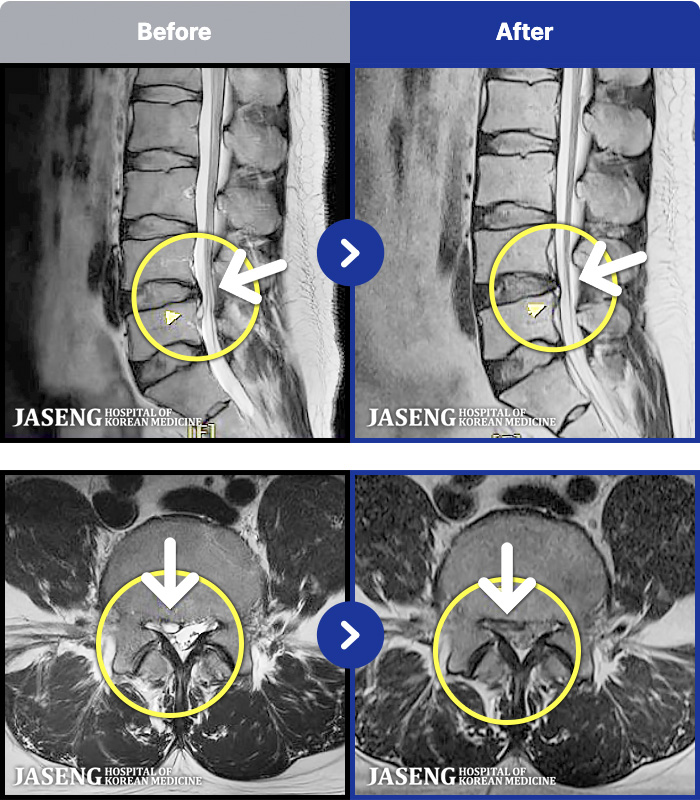

MRI ġ

MRI ũ ʸ Ȯϼ.